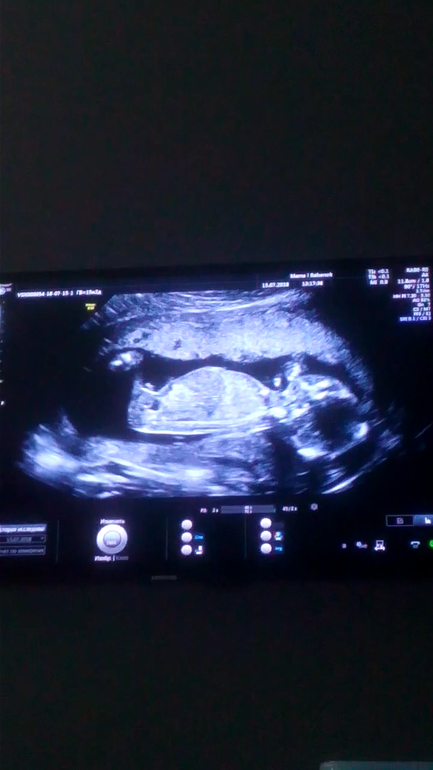

Кто видит мальчик или девочка?

Результаты: УЗИ, КТГ, доплера, скринингаВ 16 недель была на УЗИ , сказали пол мальчик, но я не знаю верить или нет ?

Точно мальчик. Видно же, мой такой же был, есть отличие с девочкой, тем более в 16 н.